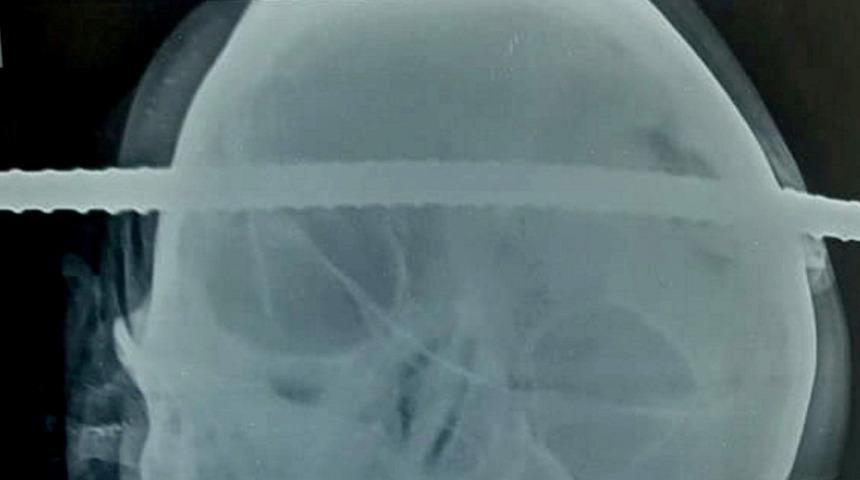

Hastaneye kaldırılan adamın sağ şakağından giren demir çubuğun beynin sol frontal bölgesinden çıktığı tespit edildi.

Adamın tansiyonu aniden düşünce ameliyata alındı ve operasyon yaklaşık 1,5 saat sürdü.

Doktorlar operasyonun mucizevi bir şekilde iyi geçtiğini ve demir çubuğun adamın kafasından çıkarıldığını aktardı.

Adamın sinus trombozuna milimetreler kala büyük bir felaketten kurtulduğu belirtildi.